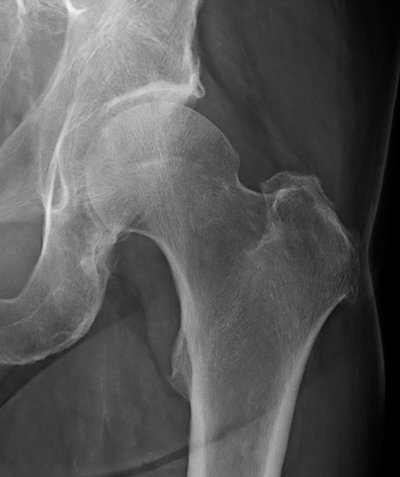

Behandlungsbeispiel

Die Orthovolttherapie ist eine schmerzfreie, nichtinvasive Behandlung mit speziellen energetischen Röntgenstrahlen.